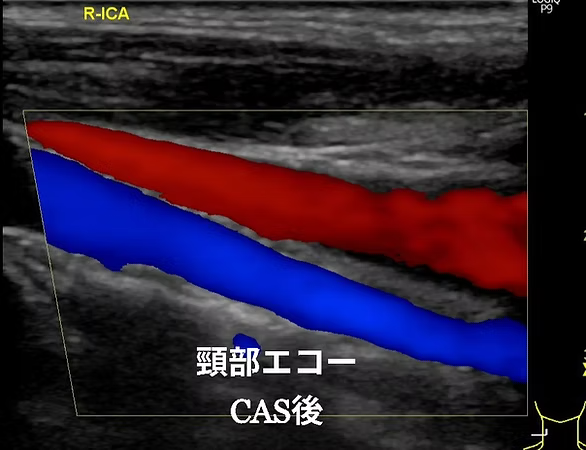

頸動脈エコー、心臓エコー、下肢静脈エコーの検査を行っています。頸動脈エコーは首の中にある頸動脈を観察し、動脈硬化のために血管が傷んでいないか、血液の流れが悪くなっていないかを調べる検査です。心臓エコーは心臓の大きさや心臓の筋肉の動きを観察することによって、心臓のポンプ機能が働いているかを調べます。下肢エコーは太ももからくるぶしにかけて静脈の流れが悪くなってないかを調べる検査です。いずれの検査も痛みのない、手軽で安全な検査です。

頸動脈エコー